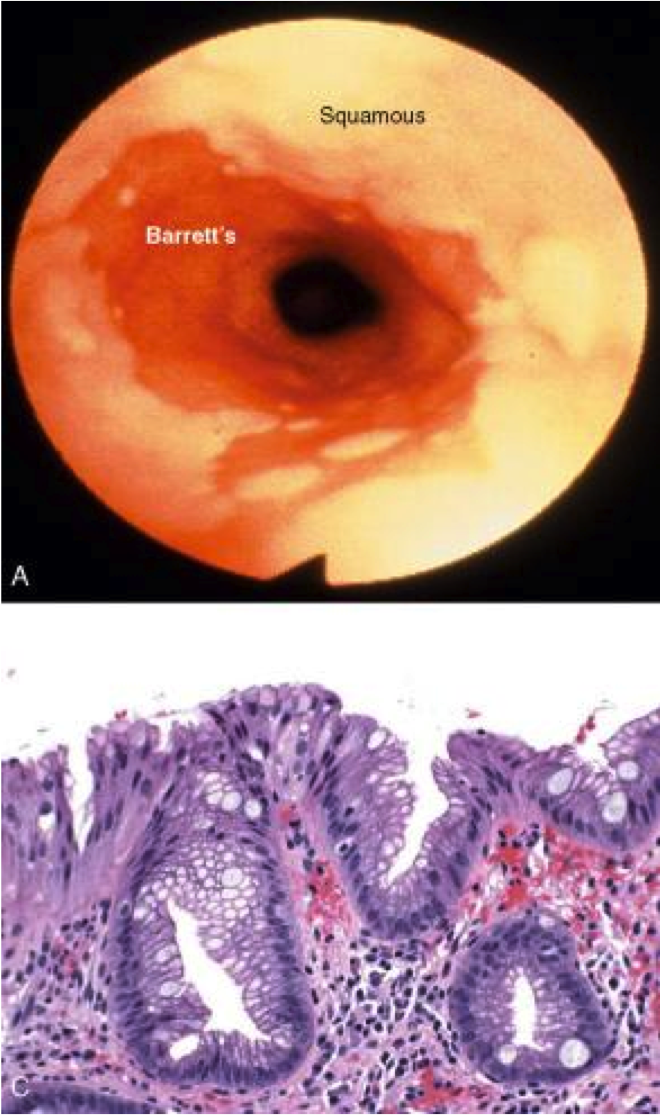

Barrett’s esophagus

Def

Definition

Endoscopically recognizable columnar metaplasia of the esophageal mucosa that is confirmed pathologically to have intestinal metaplasia, the latter defined by goblet cells

Both the endoscopic and pathologic components should be present to establish BE.

Barrett’s esophagus: columnar metaplasia (intestinal metaplasia)+goblet cells